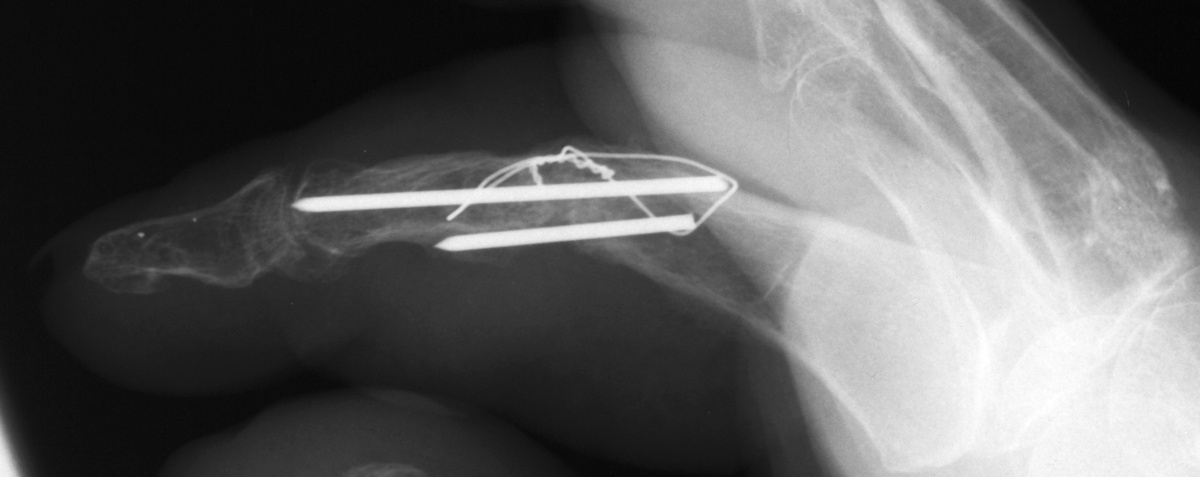

| PIP fusion with tension

band technique. |

| Late result. |